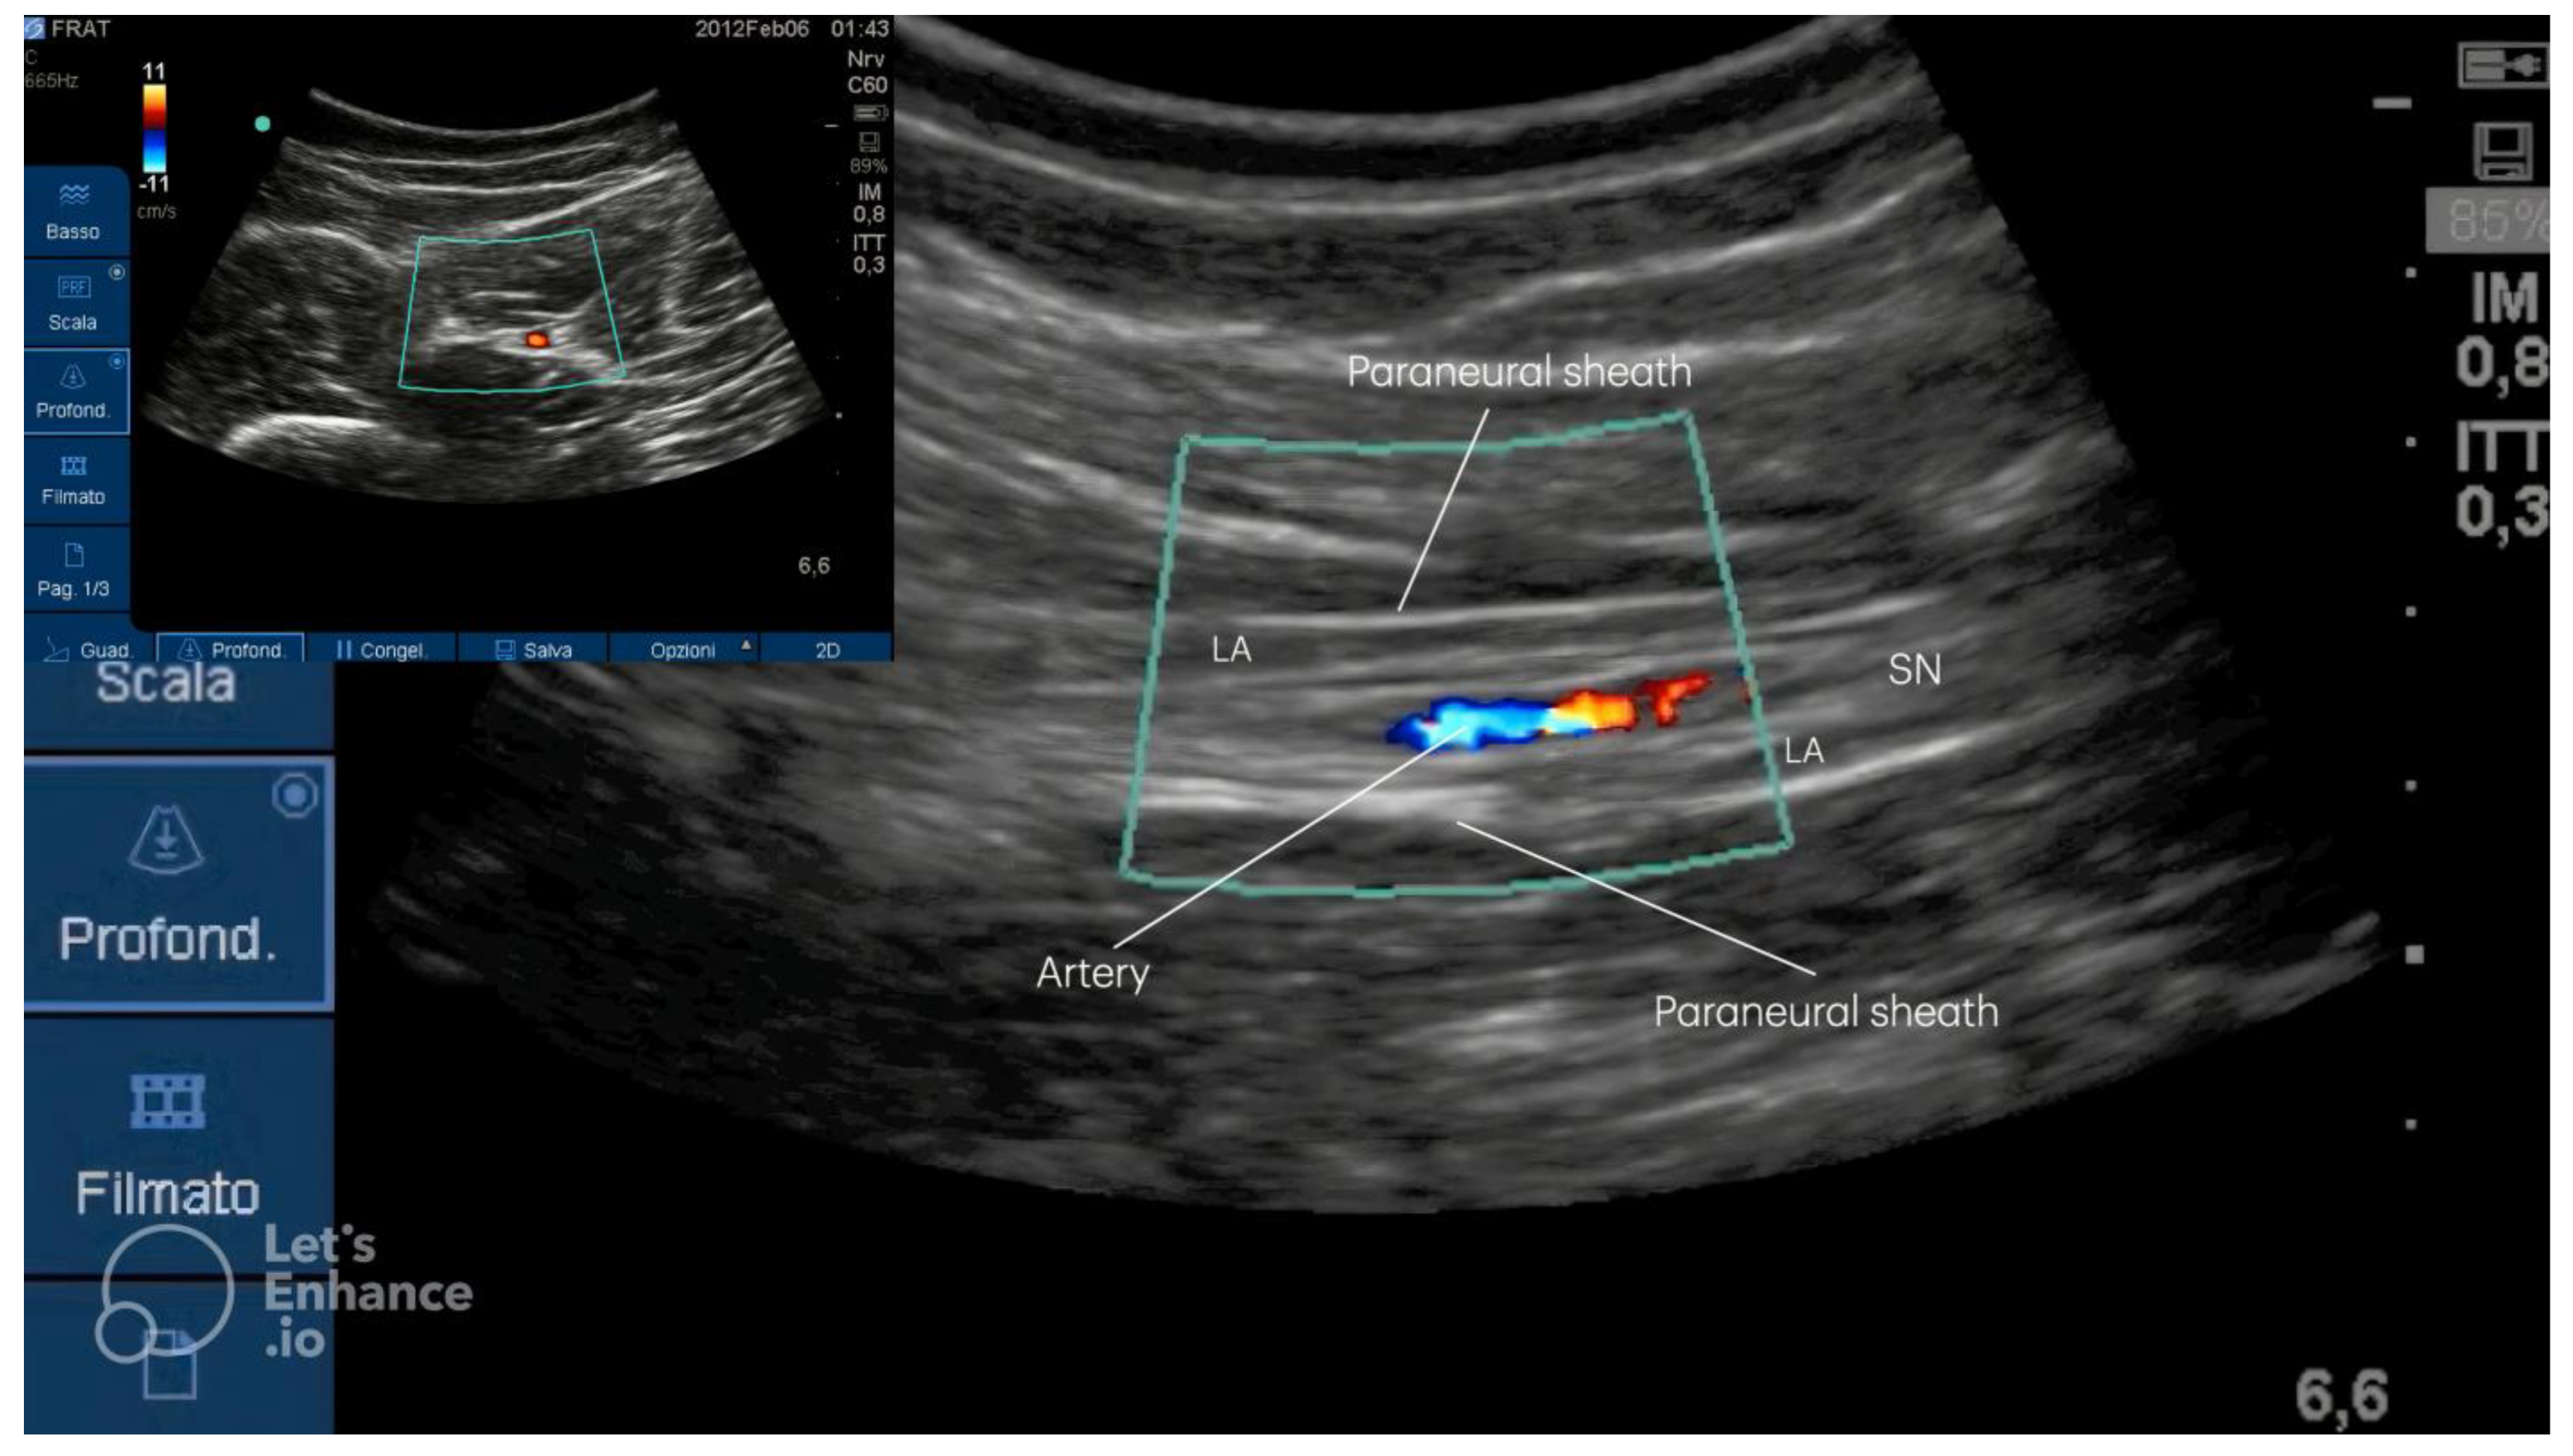

- The popliteal approach is limited by significant anatomical variability; in fact, in 53.33% of cases, the SN divides near the upper angle of the popliteal fossa; in 26.66% of cases, the division occurs in the middle of the posterior thigh, while 13.33% of cases show the division at the upper one-third of the posterior thigh; only in 6.66% of cases does the CPN pass through the piriformis muscle, with the TN situated below the piriformis muscle [15]. Moreover, the popliteal approach requires the patient to be in prone position, rendering the procedure uncomfortable for those patients affected by lower limb fractures (Figure 4A) [2].

- The original lateral approach requires the patient to adopt a supine position with the leg bent, a lateral to medial needle direction, and the probe placed below the thigh with a posterior to anterior ultrasound beam used, similar to the popliteal approach performed with the patient in a supine position. The challenges consist of the uncomfortable position adopted by both the patient, unable to flex their leg, and the anesthetist (Figure 4B) [7,9,11].